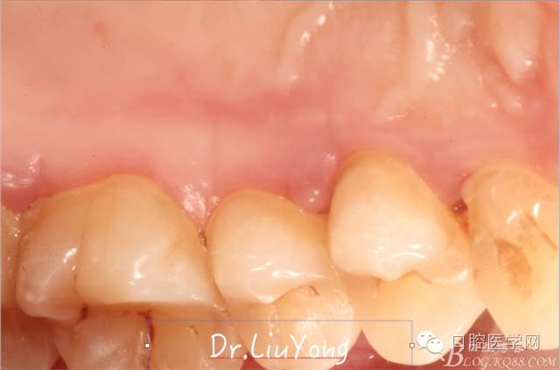

松動牙固定一月后拆除,A1-B2無明顯動度,但牙齦紅腫加重,給予全口齦上下潔治刮治術(shù),上藥,醫(yī)囑加強(qiáng)口腔衛(wèi)生,氯己定漱口液含漱。

術(shù)后兩周復(fù)查,牙齦紅腫明顯好轉(zhuǎn),探診不出血,但是此時A1唇側(cè)牙齦角形退縮1.5mm,B1唇側(cè)牙齦退縮3.5mm,B1遠(yuǎn)中牙齦乳頭萎縮明顯,B2近中牙齦萎縮約1mm,且A1B1B2牙齦退縮處角化牙齦幾乎缺失,同時上唇系帶直接牽拉于B1齦緣。患者為高笑線女性,露齦笑,由于存在前牙區(qū)牙齦的高度嚴(yán)重不對稱及前牙牙冠過長的問題,因此嘗試通過膜齦手術(shù)改善患牙牙齦退縮。通過術(shù)前分析,A1唇側(cè)牙齦退縮屬于Miller分類第一類, B1唇側(cè)牙齦退縮屬于Miller分類第3類(B1遠(yuǎn)中牙齦乳頭為2類,Nordland and Tarnow分類法),B2唇側(cè)牙齦退縮屬于Miller分類第3類,由于擬采用冠向復(fù)位瓣的方式治療牙齦退縮,因此需要先行上唇系帶修整術(shù),解除上唇系帶帶來的過大牽引力。

潔治刮治后2周,如上圖